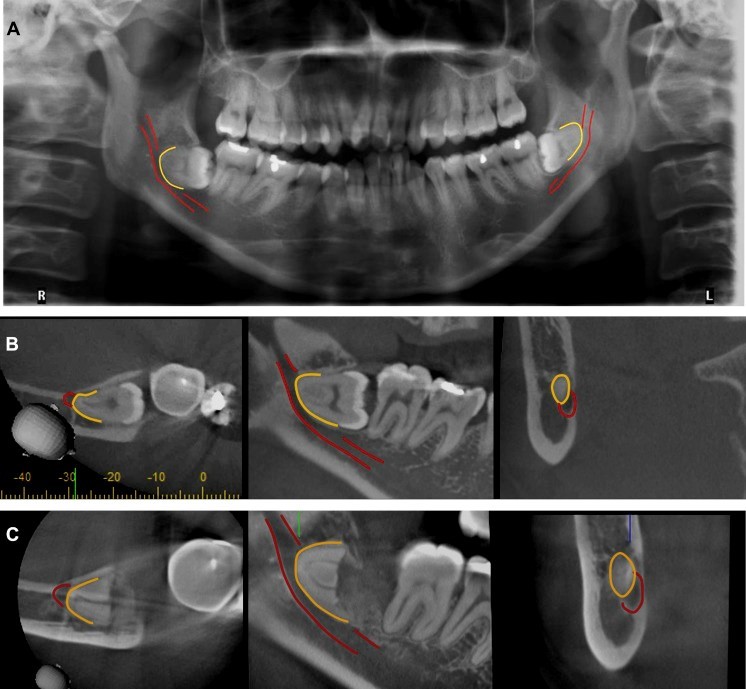

3. CBCT trong chẩn đoán răng khôn mọc lệch, mọc ngầm:

Răng khôn hàm dưới hai bên của mỗi người có đặc điểm là ít khi mọc thẳng như các răng khác trên cung hàm, có tỷ lệ cao mọc lệch hay ngầm, ảnh hưởng âm thầm đến răng phía trước nó là răng cối lớn thứ hai từ đó gây viêm lợi trùm, sâu thân răng, chết tuỷ mà bệnh nhân ít khi có triệu chứng nhận biết.

Răng khôn hàm dưới là răng trên cung hàm nằm gần với ống thần kinh răng dưới nhất và có nguy cơ cao chèn ép hay kẹp ống thần kinh, gây nguy cơ chấn thương thần kinh cao khi phẫu thuật nhổ răng khôn. Nhờ có sự giúp đỡ của CBCT, bác sĩ có thể lường trước được mối liên quan của dây thần kinh với chân răng khôn cũng như quyết định thực hiện kỹ thuật nhổ răng khôn trong một lần duy nhất hay chỉ cắt thân răng khôn, chờ chân răng trồi lên.

Răng khôn hàm dưới mọc lệch chèn ép thần kinh trên phim CBCT